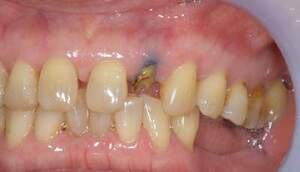

左の写真は歯が歯肉縁上にないのがわかります。右では歯肉縁上に1周にわたって歯牙があるのがわかります。

レントゲンで見ても、右上2では歯質が歯肉縁上にのこっていない。しかし歯根は長いのでMTMの適応症例です。